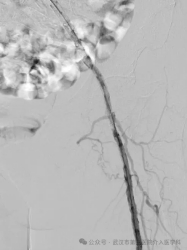

术中支架造影

支架后造影图

手术非常成功!术后当天,李奶奶就感觉那条“冰腿”变暖了,折磨她许久的静息痛也大大减轻。

虽然发黑的脚趾未能保住(进行了小范围截趾),但通过后续的慢创修复治疗,我们成功地保住了她的整条腿和脚的大部分功能!她终于可以再次下地行走了。